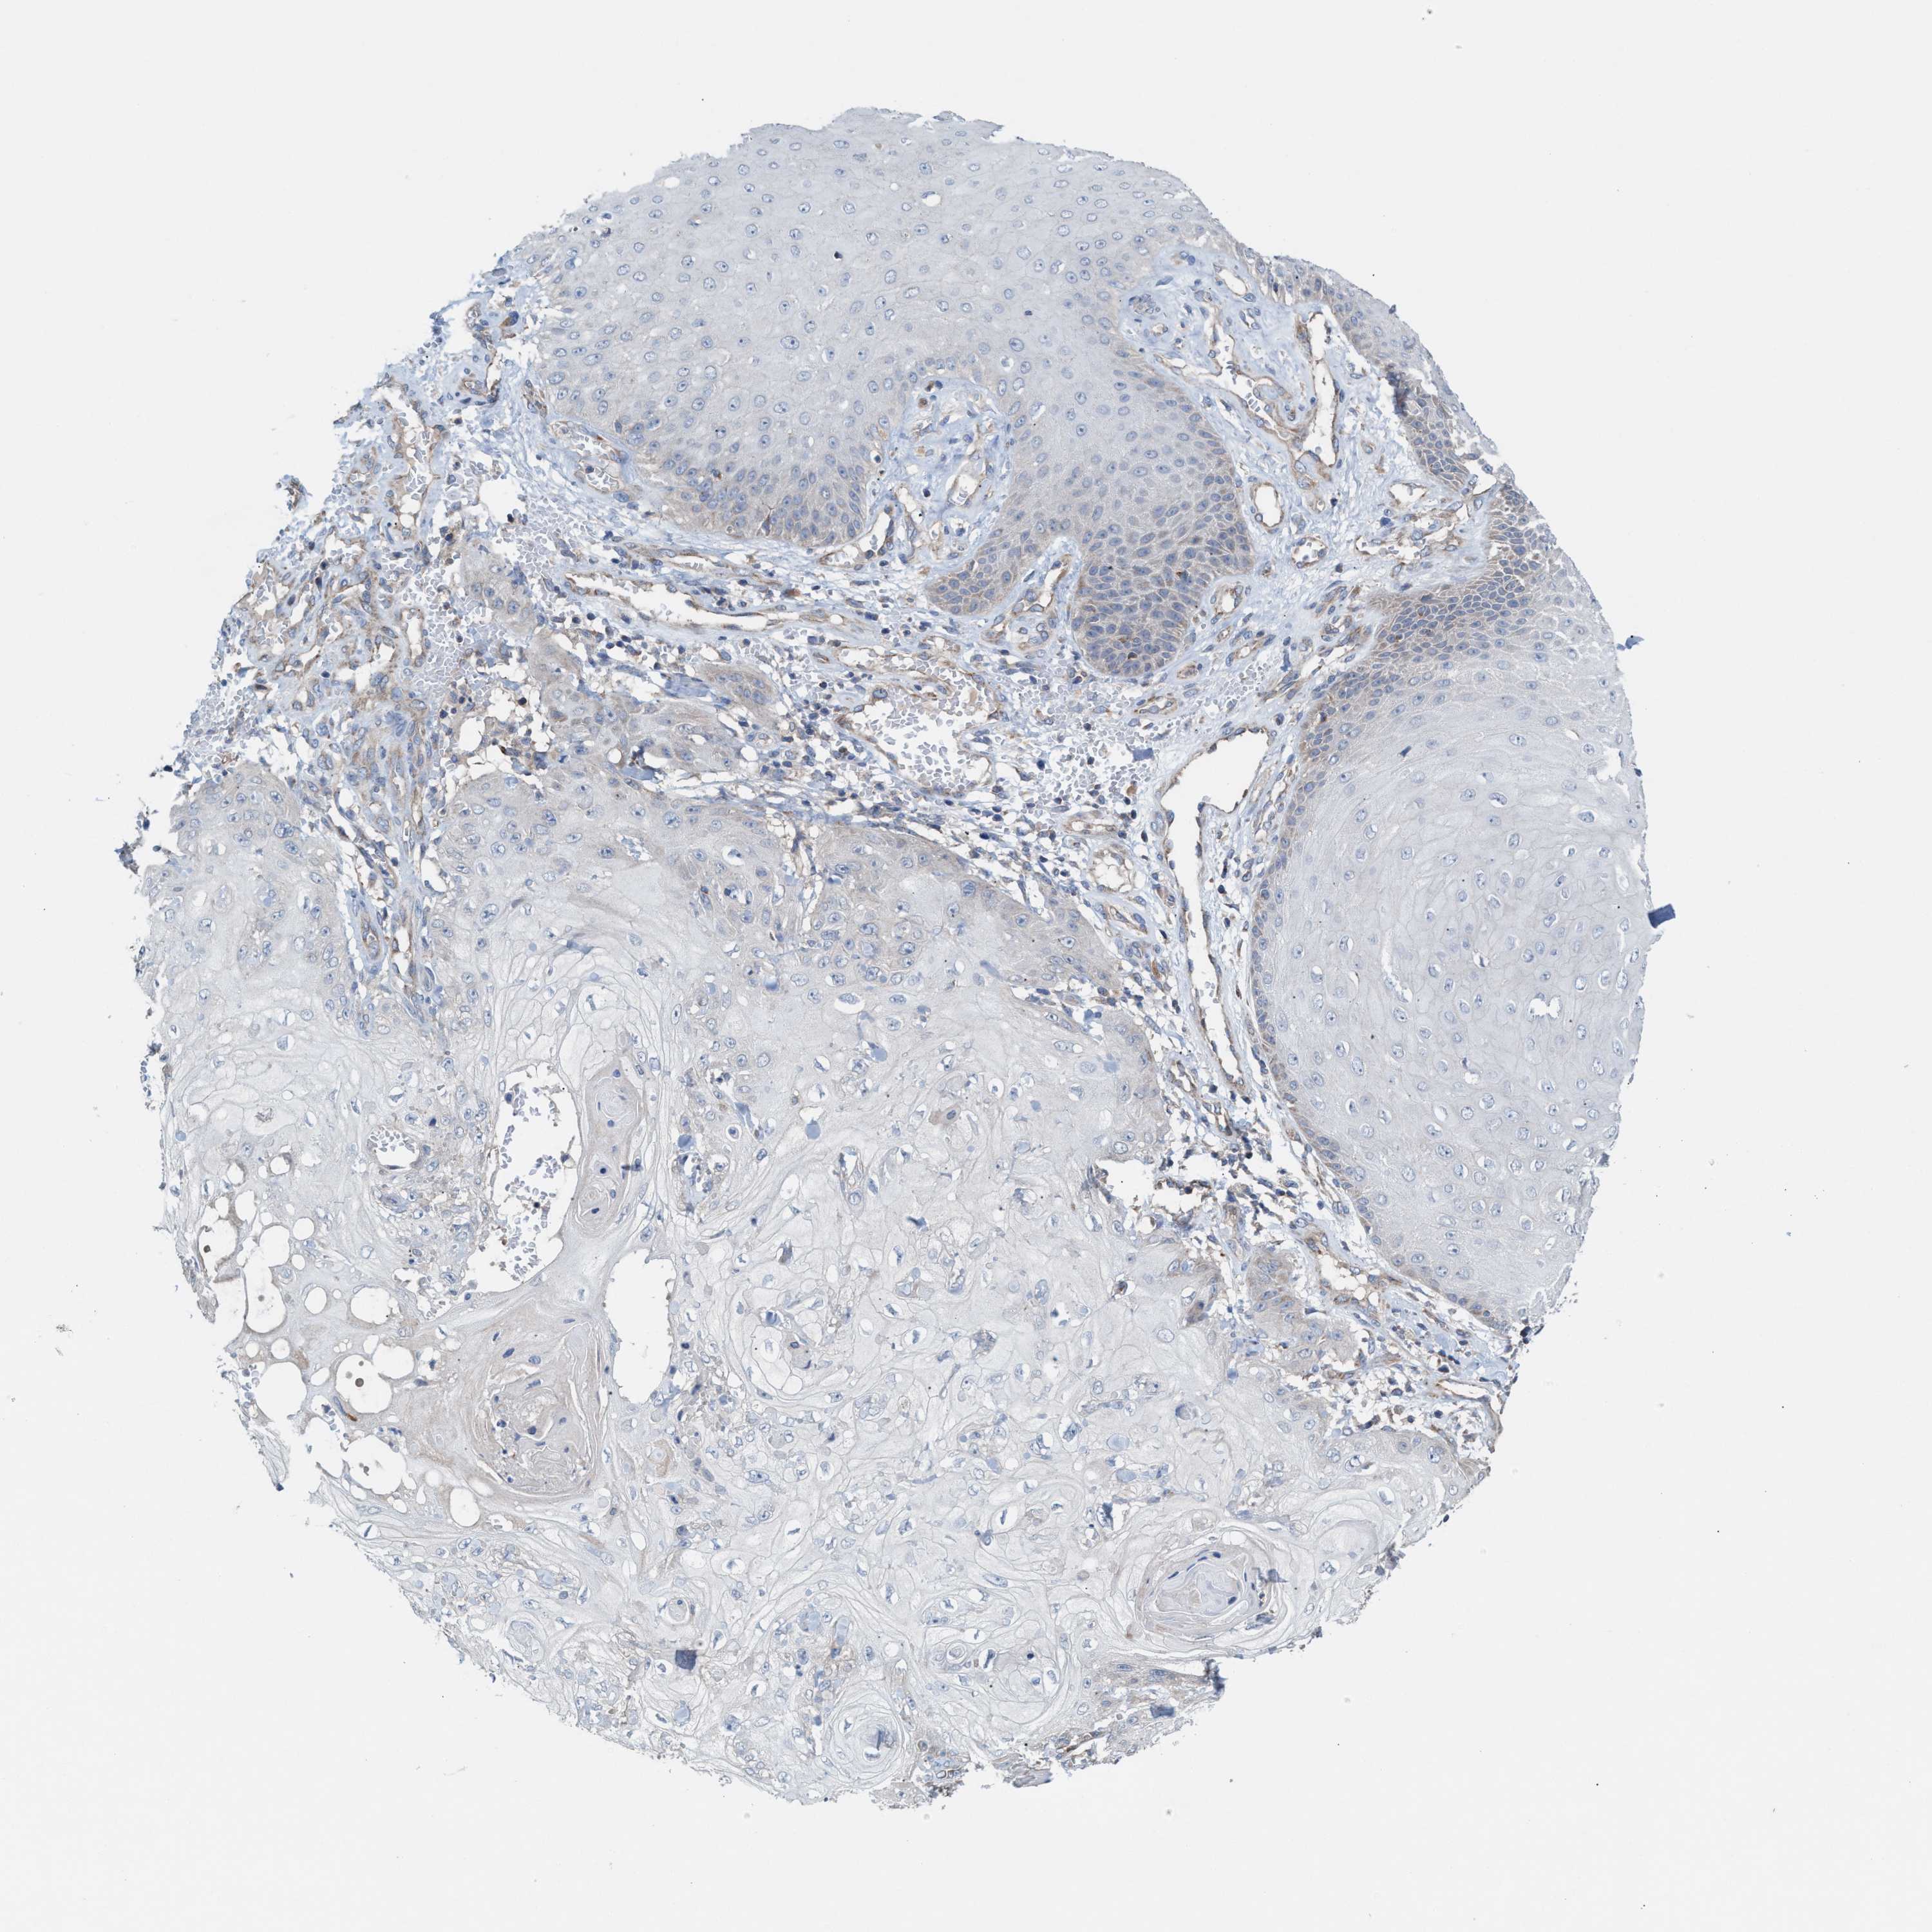

SKIN CANCER - Protein expressioni

A mouse-over function shows sample information and annotation data. Click on an image to view it in a full screen mode. Samples can be filtered based on level of antibody staining by selecting one or several of the following categories: high, medium, low and not detected. The assay and annotation is described here.

Each image is clickable and will lead to virtual microscopy that enables deeper exploration of all samples and also displays staining intensity scores, fraction scores and subcellular localization as well as patient and tissue information for each sample.

Antibody HPA021598

Squamous cell carcinoma in situ, NOS

Squamous cell carcinoma, NOS

Squamous cell carcinoma, metastatic, NOS

Basal cell carcinoma

Adnexal tumor, benign